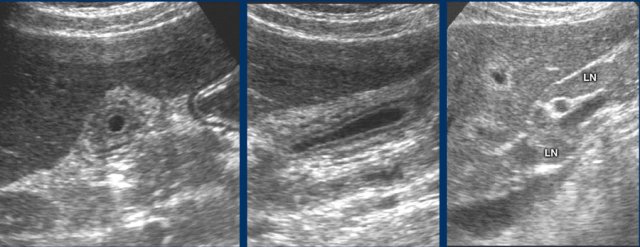

Here a patient with malaise, RUQ-pain and severe liver function abnormalities.

US shows small gallbladder with layered wall thickening and enlarged periportal lymph nodes.

Diagnosis: acute hepatitis A.